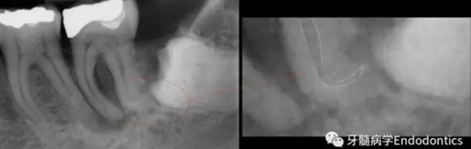

圖3.存在細(xì)小狹長(zhǎng)、可能多維的復(fù)雜根管解剖時(shí),使用10號(hào)K銼不可能立即疏通根管到達(dá)根尖止點(diǎn)。隨后醫(yī)生應(yīng)嘗試使用更小的銼探查以達(dá)到根尖。但是,通常不需要使用6號(hào)和8號(hào)K銼對(duì)到達(dá)根尖的引導(dǎo)通道進(jìn)行擴(kuò)大,除非是特別困難的病例。

圖4.根尖孔通常比10號(hào)K銼大,因此感到任何阻力時(shí)可能是因?yàn)楦艿膹澢虿灰?guī)則。因此,有效的建立可重復(fù)的引導(dǎo)通道的方法應(yīng)是使用10號(hào)K銼逐步擴(kuò)大開放根管,此時(shí)也將產(chǎn)生臺(tái)階或根管堵塞的可能性降到最低。

圖5.探查時(shí)銼不能向根尖方向用力,因?yàn)樾纬膳_(tái)階的風(fēng)險(xiǎn)會(huì)顯著增加。如果銼的尖部從未卡入根管壁,是不可能形成臺(tái)階的。